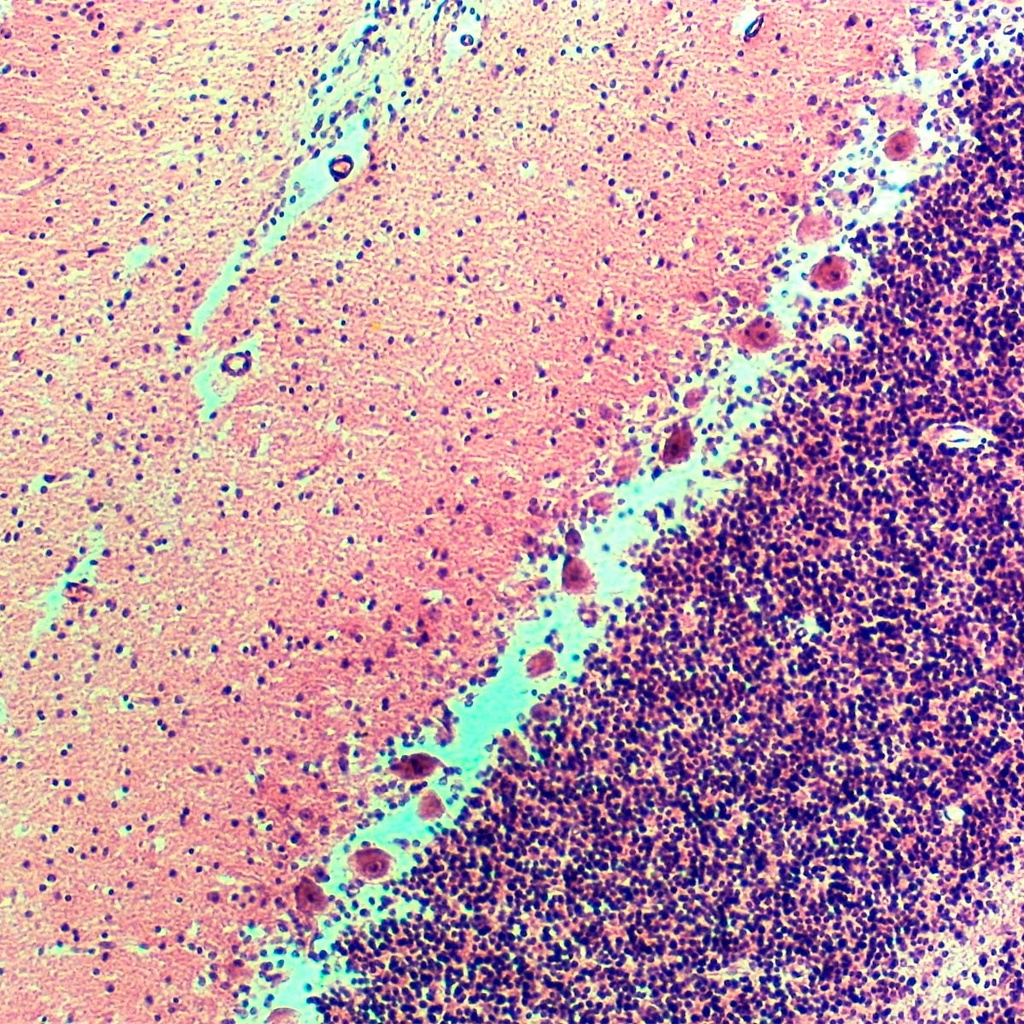

Cerebelo mamifero

Imagen ilustrativa. El producto puede variar en color, forma o presentación.